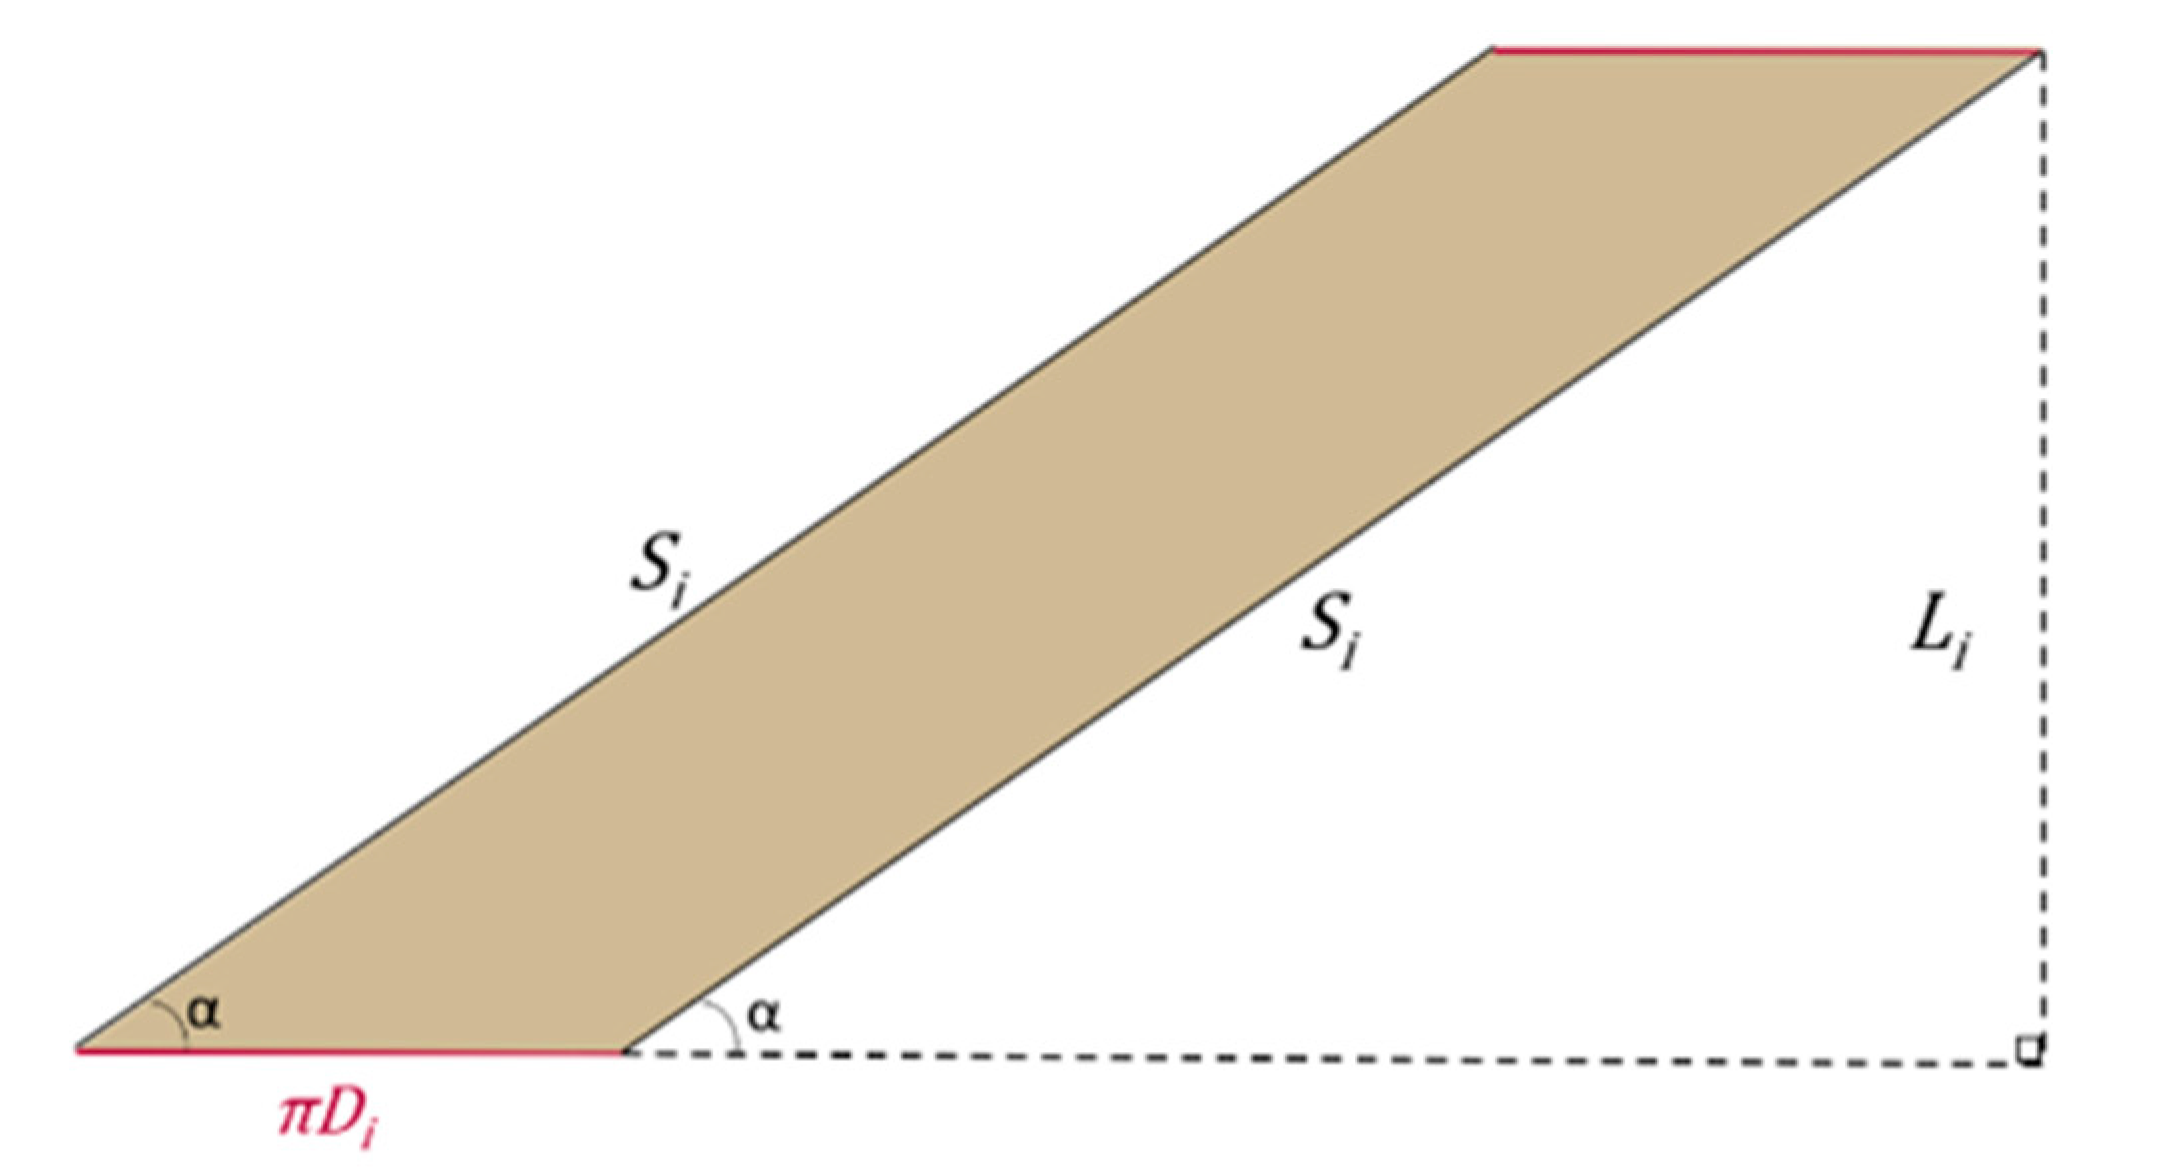

2.1. The Geometry of the SILT Procedure